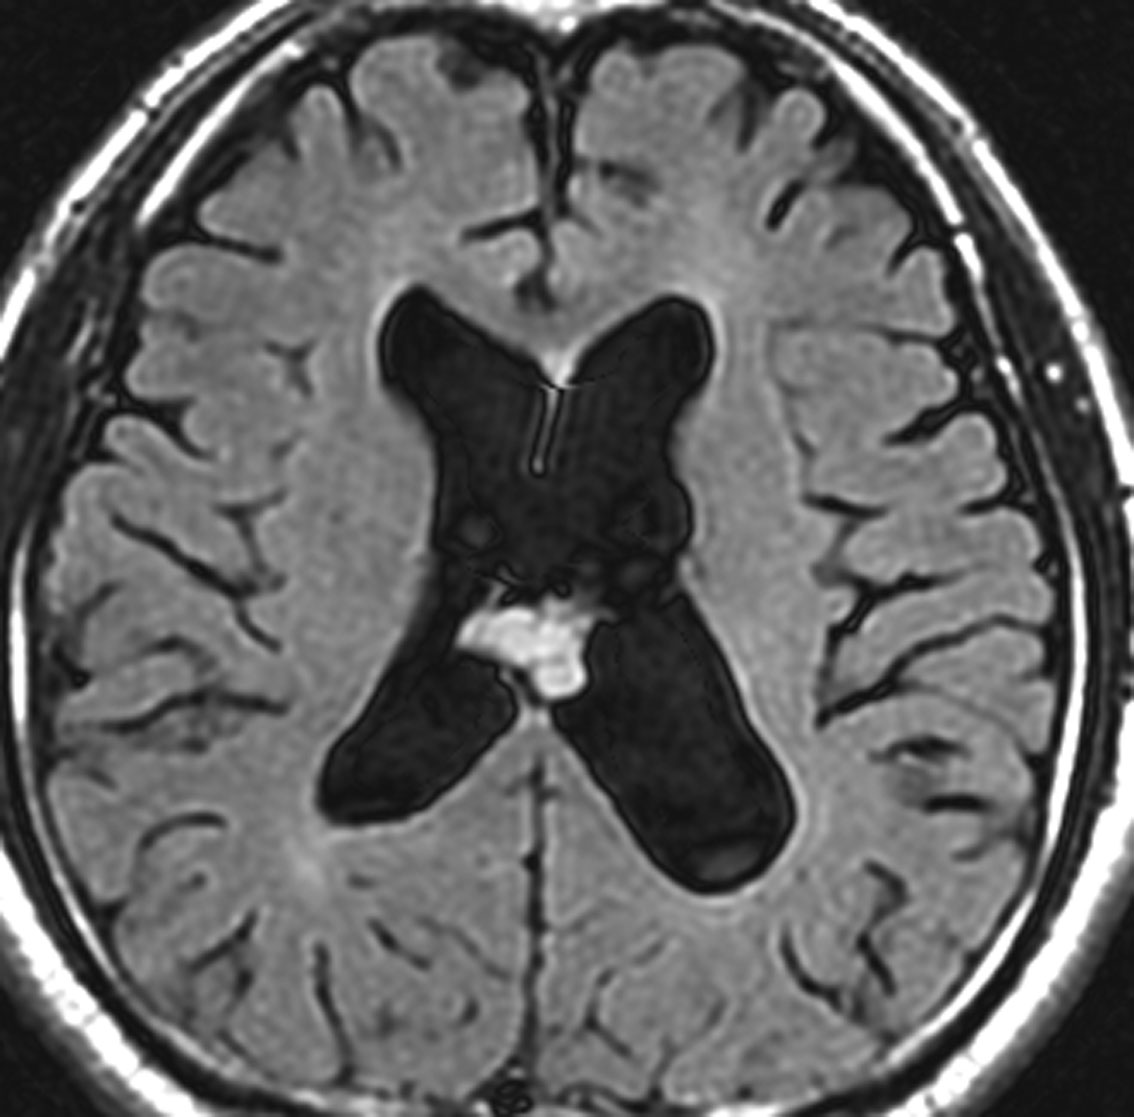

よくみつかる典型的な例です

中年男性に偶然発見された15mmくらいの上衣下腫です。側脳室前角の壁にピッタリくっつくようにキノコのように生えています。下の2枚はガドリニウム造影ですが増強されないのが特徴です。この点で中枢性神経細胞腫 central neurocytomaと区別できます。中枢性神経細胞腫はゆっくりですが大きくなる腫瘍です。でもこのような上衣下腫は大きくなるのはとてもまれです。小さいし水頭症にもならないので,なにも治療しないでほっておきます。間違っても開頭手術などしません。